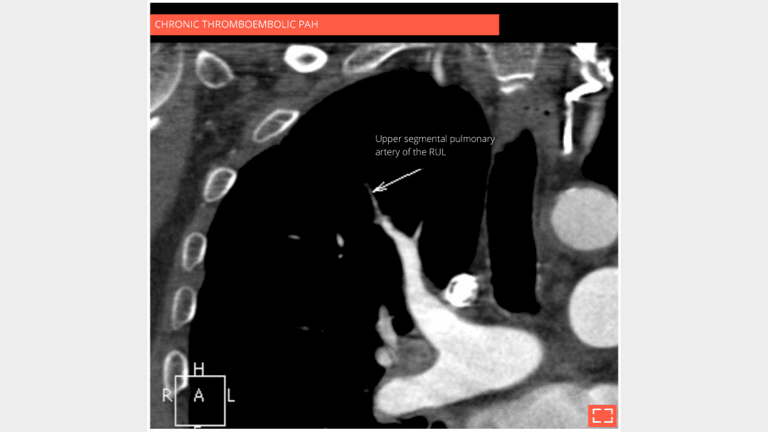

2. Vascular mosaic attenuation

Vascular mosaic attenuation

The CT scan with contrast medium injection to check for pulmonary artery obstruction shows the small size and distal thrombosis of peripheral pulmonary arteries, confirming chronic thrombosis. Ventilation-perfusion scintigraphy is the recommended exam for screening for these anomalies.

3. Vascular mosaic attenuation